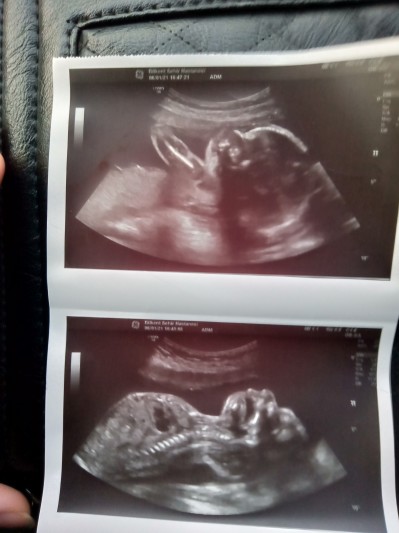

Ben Ankara şehir hastanesinde çektirdim ama 19 haftalıkta gittim gec kalmışsınız dediler ama son 1 yer boştu 22.haftaya randevu alabildim zar zor , detayli incelediler kaşı gözü olarak görünmüyor ama şekli belirgin görünüyor daha detayli için özel hastanede yaptırmak lazım renkli olarak , aşağıda bak görüntüsünü attım bu fotoğrafı verdiler

image

kolunun üzerine yatarken yakalayabildik foto çok hareketliydi

Attım yoruma görüntüyü canım

Oy maşallah kaç haftaliktiniz inşallah bizimkide böyle net çıkar ya

(84 puan)

20+4ken çektirdim canm